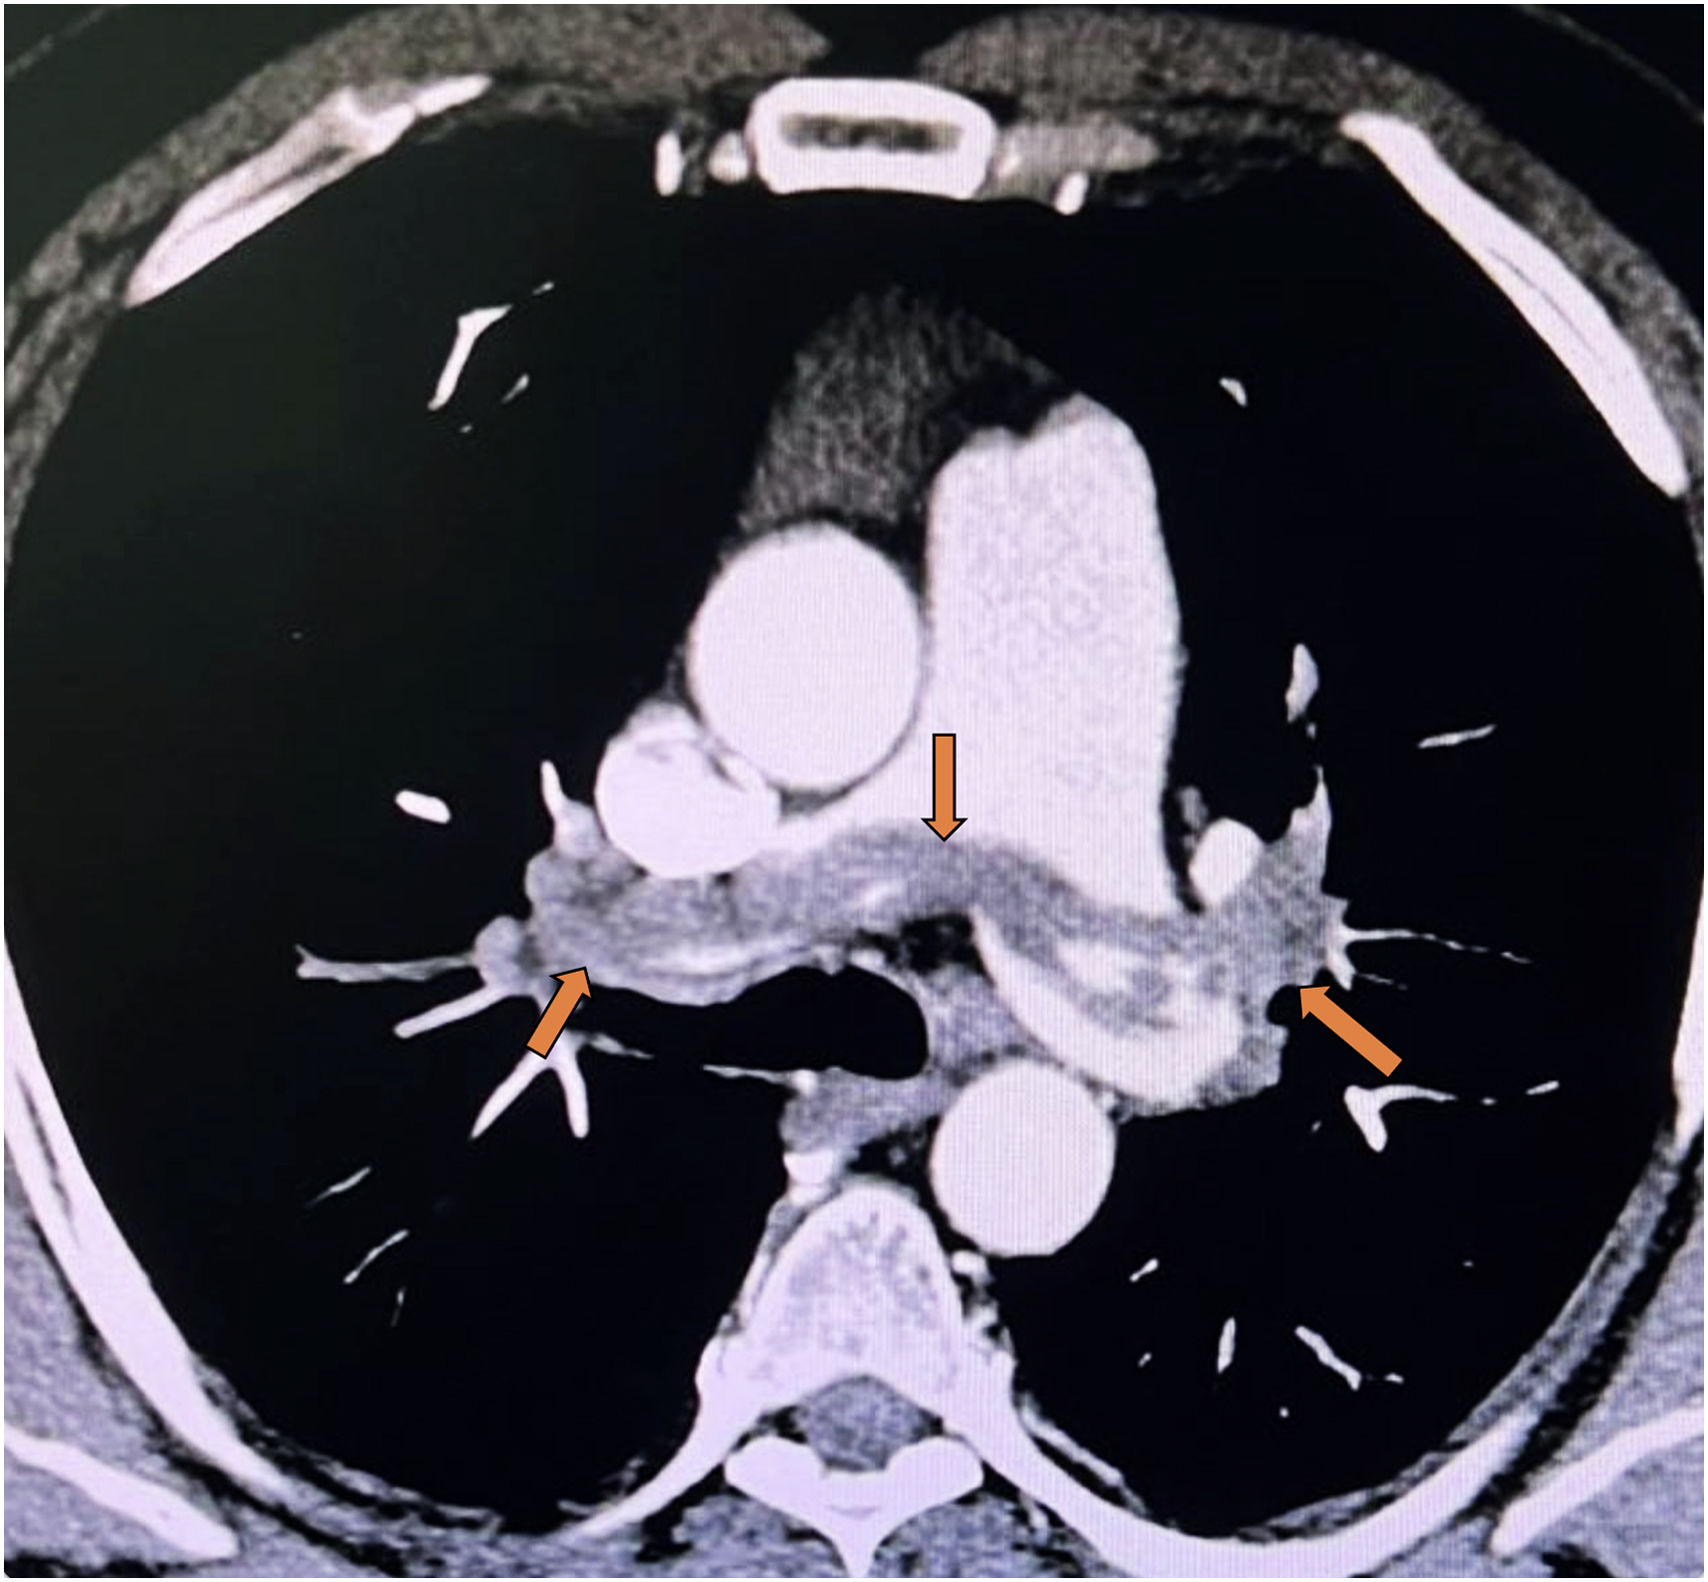

Within this spectrum, saddle pulmonary embolism (SPE) has traditionally been perceived as synonymous with “massive” or high-risk PE because of its striking central clot burden on computed tomography pulmonary angiography (Fig. 1). However, contemporary series and meta-analyses suggest that SPE is a heterogeneous phenotype with variable outcomes and a nonconsistent independent association with 30-day all-cause mortality once right ventricular (RV) function and hemodynamic status are taken into consideration [2,3]. The work by Briceño et al. reinforces the notion that clot location and burden are, at best, imperfect surrogates of clinical severity and should not replace a comprehensive risk assessment grounded in RV dysfunction, biomarkers, and comorbidities.

CT pulmonary angiography in a hemodynamically stable patient showing a bulky saddle embolus straddling the bifurcation of the main pulmonary artery and partially obstructing both main pulmonary arteries (red arrows) – an appearance traditionally associated with ‘massive’ or high-risk pulmonary embolism.